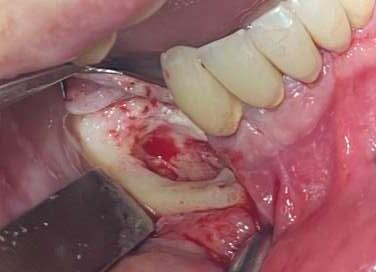

Trattamento dell’osteonecrosi mandibolare da bifosfonati

Ancora oggi non esiste un protocollo univoco di trattamento di questo tipo di complicanza e le motivazioni di questa assenza risiedono nella enorme variabilità della casistica tra paziente e paziente.

Ci sono però dei punti fermi su cui è ormai scontato che si debba fondare il proprio operato: pulizia, garantita dalla detersione profonda con l’utilizzo del PiezoClean®, e stimolazione alla guarigione indotta dal PRGF®3

La correlazione tra l’assunzione di bifosfonati orali e la comparsa di necrosi mandibolare è certa, così come certa è l’urgenza con cui è necessario intervenire su questo tipo di complicanza. Intercettare precocemente la problematica è possibile attraverso il follow-up. Appurata la presenza di una necrosi ossea, è indispensabile fornire all’organismo del paziente le corrette molecole antibiotiche per il trattamento e la prevenzione delle infezioni del sito chirurgico. Le complicanze di un mancato trattamento sono infatti gravi (es. compromissione del nervo alveolare, frattura di mandola, comunicazioni bucco-sinusali)2

La paziente è una donna di 73 anni, in terapia con denosumab e corticosteoidi per il trattamento dell’artrite reumatoide.

È giunta per un ascesso con presenza di fistola drenante nel 4° quadrante ed è stata sottoposta a CBCT che ha rivelato la presenza di una necrosi mandibolare nella zona interessata dalla problematica ascessuale.

La necrosi, in estensione da 4.5 a 4.7, era stata precedentemente trattata con riabilitazione su impianti; sulla base di ciò è stata impostata la terapia antibiotica combinata con Amoxicillina+ac. Clavulanico e metronidazolo.

Mediante l’esecuzione di un lembo trapezoidale è stato possibile avere accesso all’intera zona necrotica, con buona visibilità del campo, nonostante la scarsa apertura buccale.

Dopo aver scollato ed esposto la zona, mediante l’uso dello strumento ultrasonico si è rimossa la porzione necrotica.

Per questa azione di toelettatura sono stati adoperati gli inserti Esacrom ES052XGT e ES010T.

Verificata la completa rimozione del tessuto malato e appurato il ripristino della vascolarizzazione del sito, è stato ulteriormente deterso mediante una applicazione della durata di 60 secondi dell’inserto PIEZOCLEAN, il cui utilizzo produce detersione profonda della zona su cui viene applicato. Infatti il dispositivo, in silicone sterilizzabile in

Al termine della toelettatura, sono state posizionate le due frazioni di PRGF e si è effettuata sutura interna con Vycril 4/0 ed esterna con seta 4/0.

L’immagine finale mostra lo stato della mucosa a distanza di 1 anno.